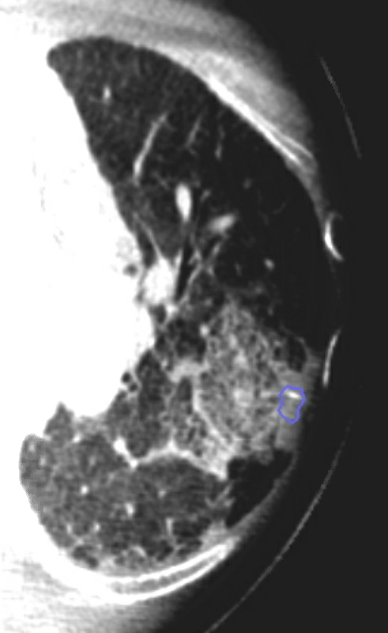

Ramsy Abdelghani, MD@Rabdelgh·

Growing LUL pleural based lesion with no airway leading to it and negative on IR biopsy. Was able to navigate close (within 2cm) to the lesion, biopsy, and adjust using CBCT. Positive for poorly differentiated carcinoma. I would have never tried this without CBCT and Robotics.